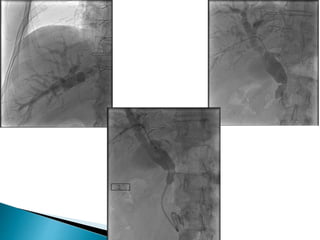

A Initial cholangiogram reveals stricture in the common hepatic duct near the previous

surgical clips.

b Balloon dilation of stricture.

c Placement of multiple stents over two procedures.

D Cholangiogram after stent removal showing stricture resolution.

Endoscopic treatment of post-cholecystectomy

biliary stricture using plastic biliary stents.